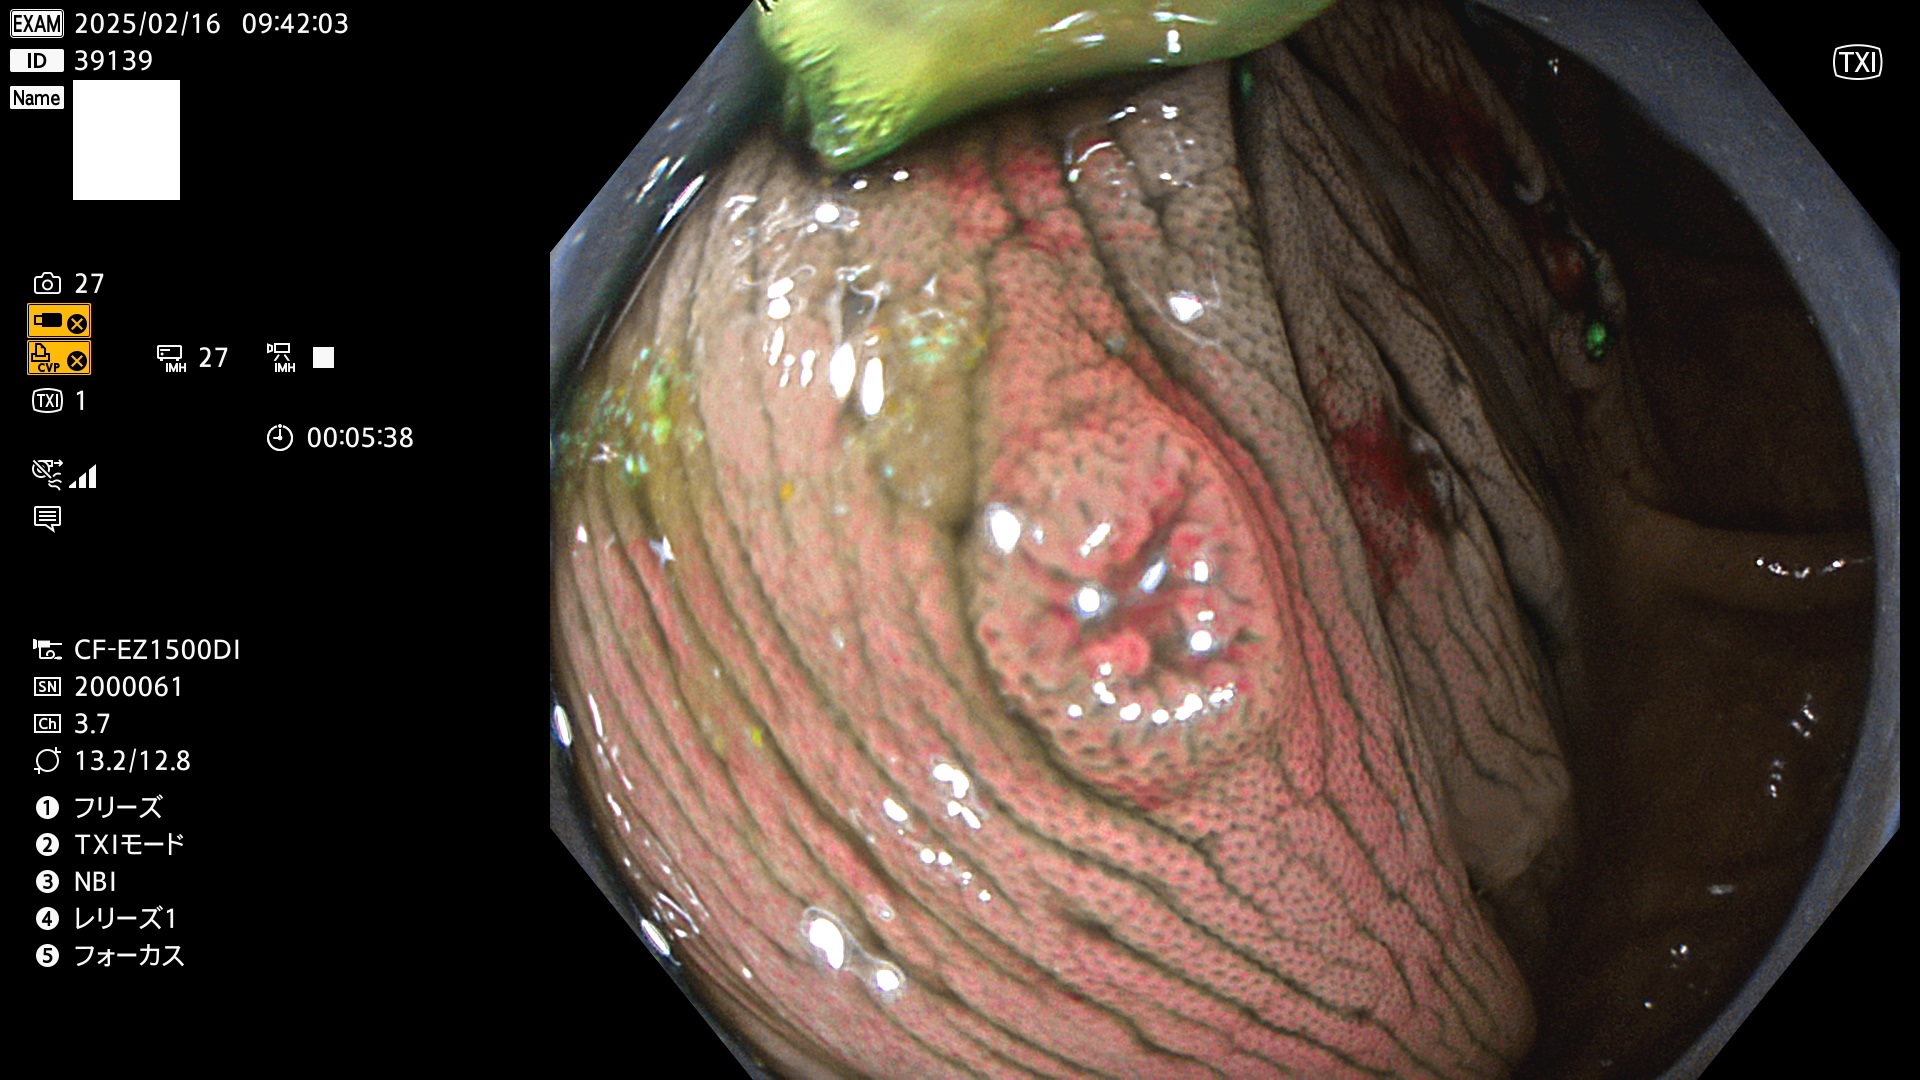

今週のUb、Uc型腺腫

完全に平坦な物をUb、陥凹している物をUcと呼びます。最も発見が難しく危険な病変です。

毎週の検査(木・金・土・日)に発見されたUb、Uc型・腺腫を、その週の日曜の夜にUPし1週間、提示します。

抽出の対象期間 2025年2月13日〜2月16日の4日間(48件の検査)8個 (8/48=16%)